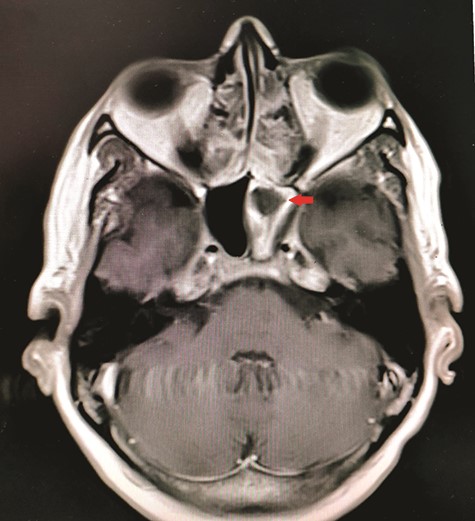

CT unveiled calcified densities within areas of hypoattenuation in the left sphenoid sinus. No marked bony destruction was observed (Fig. 2). A subsequent magnetic resonance imaging (MRI) was carried out to show hypodensity on T1 weighted post-contrast, and flow void in T2 weighted images within the same sinus (Figs. 3 and 4). Following informed consent, an emergency endoscopic left trans-ethmoidal sphenoidotomy was performed under general anaesthesia. A dense, darkened clay-like mass surrounded with the mucopurulent discharge was noticed within the left sphenoid sinus. The mucosa appeared inflamed and oedematous without clinical evidence of frank necrosis. The debris was utterly removed with a curette and sent for evaluation. The left sphenoid sinus was widened and thoroughly rinsed.

Axial view of MRI T2 weighted revealed flow void signal within the left sphenoid sinus.